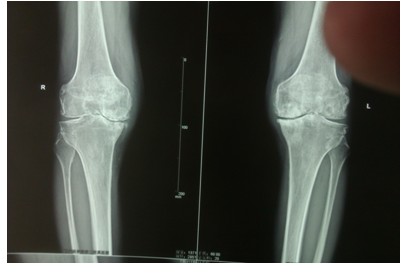

关节骨科组:我院是全市最早开展关节置换的医院之一(1987年开展全髋关节置换手术,2003年开展肩关节置换手术,2007年开展全膝关节置换手术)以治疗各类关节疾病为特色,成功开展人工关节置换术,包括对股骨颈骨折,膝关节骨折和退变等进行人工(全)髋关节,膝关节及肩关节置换等手术,已达国内先进水平;对高龄患者股骨粗隆间粉碎性骨折的人工关节置换,股骨头无菌性坏死晚期人工关节置换,全髋关节翻修术等诸多疑难复杂的人工关节置换,翻修术积累了丰富经验。

多阶段颈椎损伤